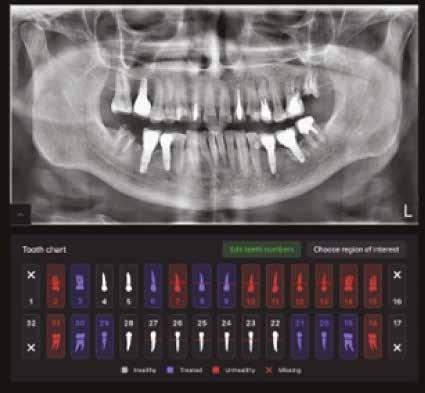

A mesterséges intelligencia és a digitalizáció már most is jelentős előnyöket nyújt a fogorvosi gyakorlatban. Az ideális végállapot előre tervezhetősége, a precizitás növelése és a műhibák minimalizálása nem csak a sikerarányt javítja, hanem a fogművek élettartamát is növeli. A technológiai fejlődés előtt ugyanakkor hazánkban két akadály áll. Egyrészt sok rendelő nem engedheti meg magának a magas anyagi befektetést, másrészt ezeknek a rendszereknek a klinikai munkafolyamatokba történő integrálása jelentős időráfordítást is igényel. A digitális munkafolyamatok és a mesterséges intelligencia valóban hatékonyabbá tehetik a munkánkat, de alkalmazásuk komoly tanulási görbét jelent, és nem helyettesítheti az orvos szakértelmét sem. Ez utóbbira mondok egy példát:

a mesterséges intelligenciát már diagnosztikai szoftverekben is alkalmazzák, például röntgenképeken felismeri a léziókat, de az elváltozásokat végső soron nekünk kell jóváhagynunk vagy korrigálnunk.

Új dimenzió a CBCT, a fogászati röntgenek és a kefalometriai felvételek diagnosztikájában a MESTERSÉGES

Dentális státusz elemzése mesterséges intelligencia által CBCT felvételen.

Panorámaröntgen elemzése mesterséges intelligencia által.